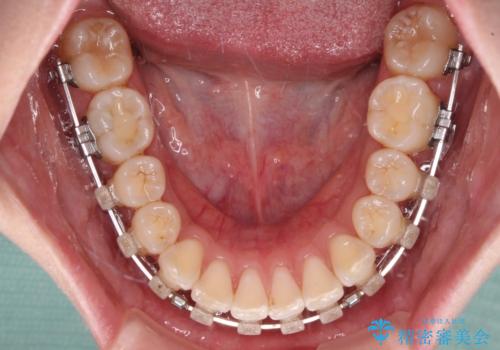

- 矯正装置

- クリアブラケット

- 2年2ヶ月

骨格的に上顎骨が前方位にあるため、左右の第一小臼歯を抜歯し、ワイヤー装置にて咬み合わせを整えていくこととしました。

前歯の突出感が改善されるだけでなく、奥歯の咬み合わせも改善され、食いしばりをしにくい状態に仕上げることができました。